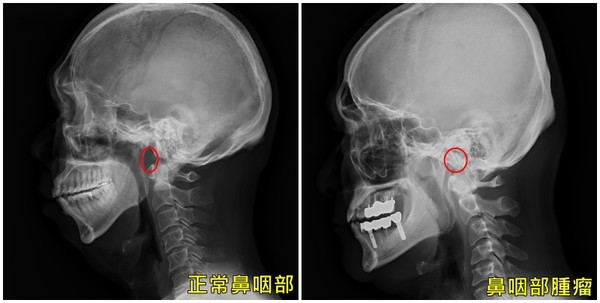

Bác sĩ Trần Lượng Vũ, trưởng Khoa ngoại cổ của Bệnh viện Đại học Á Châu cho biết, kiểm tra sơ bộ ban đầu cho bệnh nhân phát hiện, màng trong mũi của bệnh nhân chỉ hơi uốn cong, phía dưới xương xoang mũi cũng không quá dầy, nên không phải là nguyên nhân chính gây nghẹt mũi. Ngay lập tức bác sĩ nội soi cho ông Trương phát hiện, hóa ra có một khối u, gần như chặn phần mũi họng, bước đầu chẩn đoán là ung thư biểu mô mũi họng giai đoạn đầu.

Bác sĩ Trần Lượng Vũ cho biết, ung thư biểu mô mũi họng là ung thư xảy ra ở vòm mũi họng, nó nằm ở sau mũi và ở trên phần sau của họng. Vòm họng là phần trên của họng, một hình ống trải rộng từ phía sau mũi tới đỉnh của khí quản và thực quản trong vùng cổ. Bệnh này xảy ra ở nam giới nhiều hơn nữ, khoảng từ 40 -50 tuổi.

Bác sĩ Trần Lượng Vũ nói, triệu chứng của ung thư biểu mô mũi họng bao gồm phần cổ bị sưng, có máu trong nước bọt, chảy máu mũi, nghẹt mũi, nghe kém, nhiễm trùng tai thường xuyên, nhức đầu…